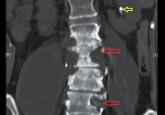

ArticlePersistent back pain in a young womanAuthor:John Samuel Banerji, MS (General Surgery), MCh (Urology), DNB (Urology)Publish date: June 1, 2015Spinal tuberculosis, or Pott disease, is still a common cause of back pain in parts of the world where the infection is rampant.Read More